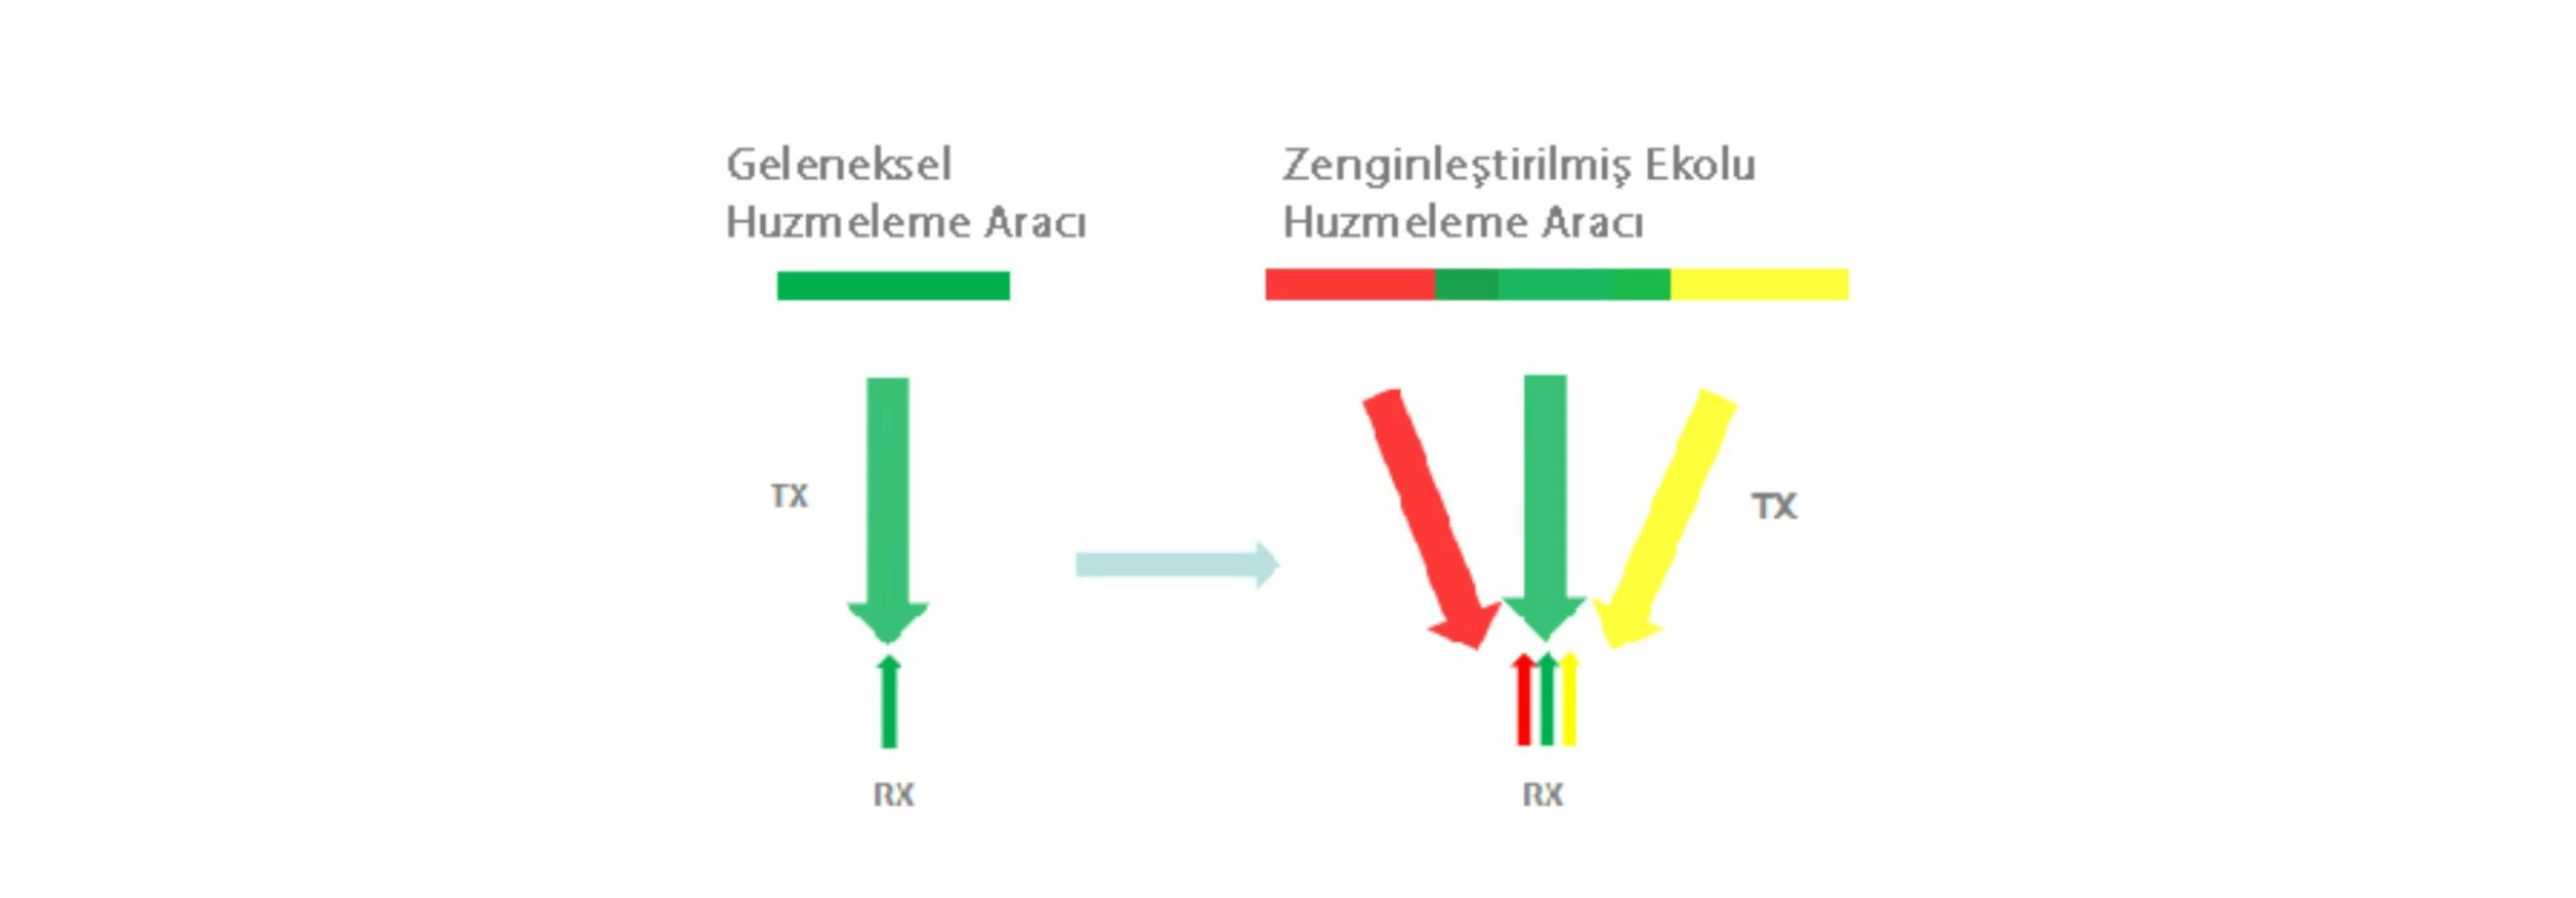

Zenginle?tirilmi? Ekolu I??n Olu?turma

Zenginle?tirilmi? ekolu ???n olu?turucu, tek bir daha ince ve daha gĂŒ?lĂŒ g?rĂŒntĂŒleme ???n? olu?turmak i?in geleneksel olarak g?z ard? edilmi? kom?u ???nlar?n eko sinyallerinin kullan?m?na izin verir, b?ylece daha iyi "hedef d???" g?rĂŒntĂŒ ??zĂŒnĂŒrlĂŒ?ĂŒ ve daha derin g?rĂŒntĂŒ penetrasyonu sa?lan?r.